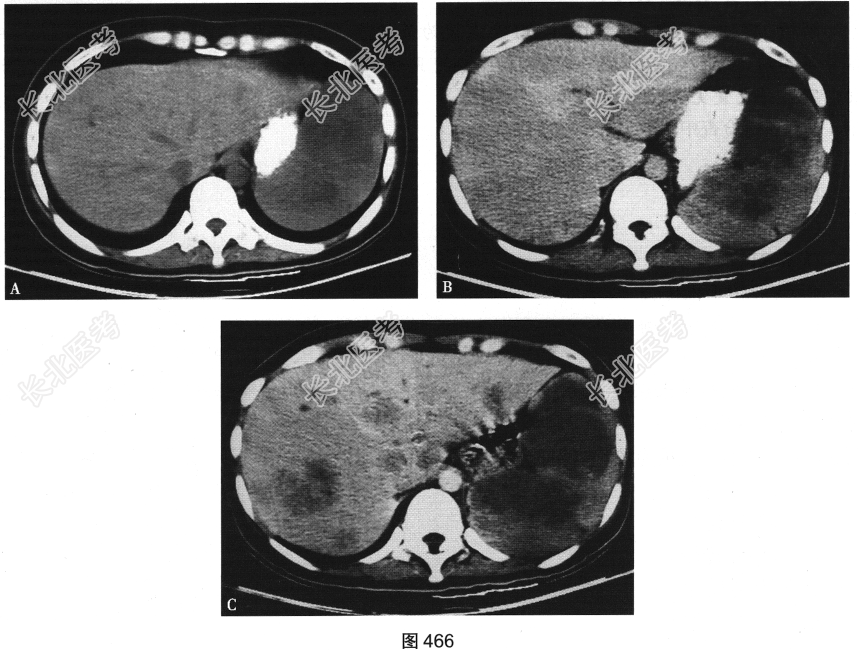

- [材料题] 患者男性,60岁,主诉腹痛2个月余,伴发热、消瘦及贫血。查体发现左上腹肿块。CT扫描见脾脏不均匀增大,内见多发低密度肿块,形态不规则,边界欠清,增强扫描呈不均匀边缘强化(图466)。

- 多项选择题2.[提示]患者行腹部CT检查,如图466所示。A、B为患者第一次检查时图像(A为CT平扫图像, B为CT增强扫描图像),C为患者45天后复查CT增强扫描图像。结合CT检查所见, 该患者的诊断为( )